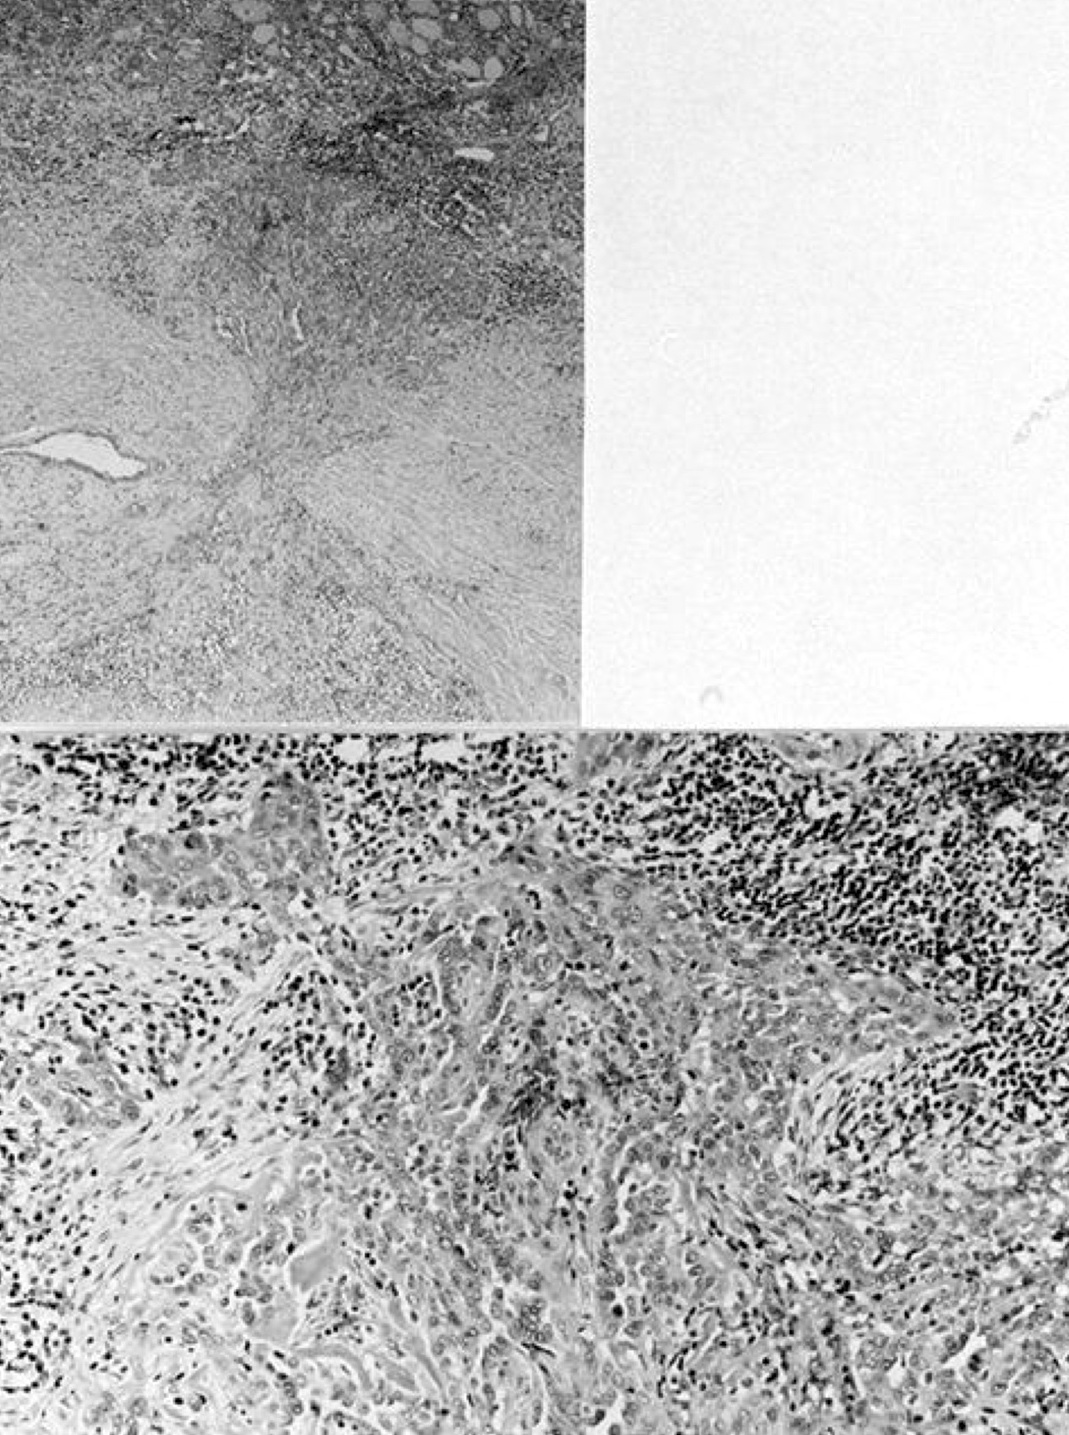

Microscopic (histologic) images

Contributed by Shipra Agarwal, M.D., Andrey Bychkov, M.D., Ph.D., Mark R. Wick, M.D., Asmaa Gaber Abdou, M.D. and AFIP

Patterns:

Atypical adenomas:

Not invasion: